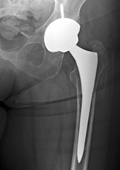

Patient developed severe groin pain 3 years after a total hip replacement done with a posterior approach and a 12 inch incision. Xrays show a loose socket component that has spun around in the bone

Patient underwent and minimally invasive acetabular revision via an anterior approach and a 4 inch incision.